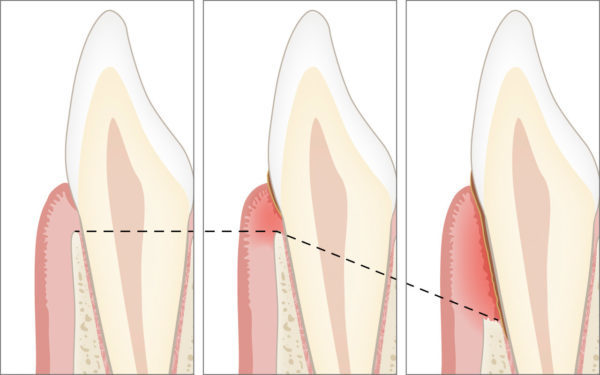

Durch den bakteriellen Zahnbelag entsteht eine Entzündung am Zahnfleischrand (Gingivitis), die sich auf die gesamte Zahnverankerung (Parodontitis) ausbreiten kann. Durch den Knochenschwund entstehen am Zahnfleischrand sogenannte Zahnfleischtaschen sowie die Lockerung der Zähne bis hin zum Zahnverlust.

Die Folgen der Parodontitis sind der Verlust der Zahnverankerung und die Lockerung der Zähne bis hin zum Zahnverlust, die auch Probleme beim Kauen verursachen können. Weitere Leiden betreffen die Allgemeingesundheit wie auch häufiger Mundgeruch oder Probleme mit dem Aussehen.